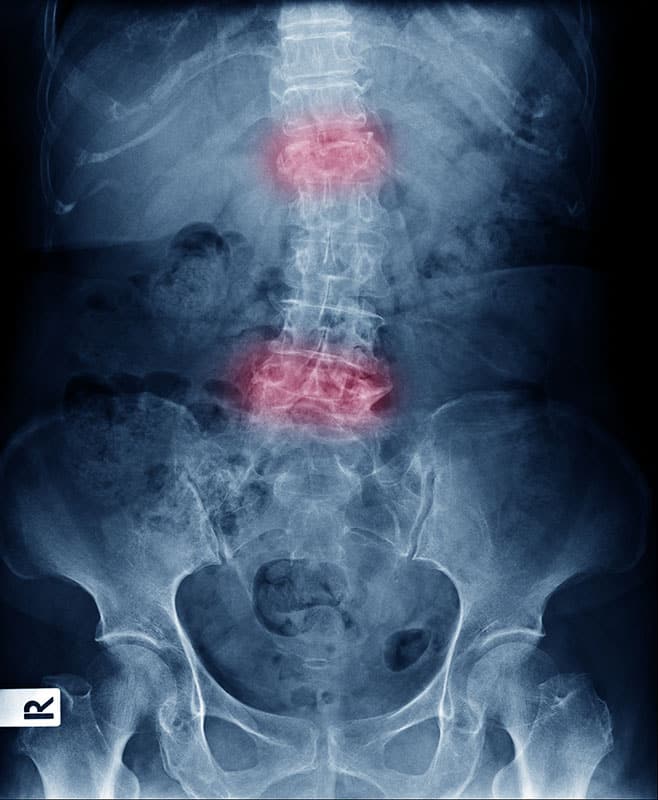

Ankylosing Spondylitis (AS) is an inflammatory disease that can cause vertebral bones in the spine to fuse over time. This fusing causes the spine to lose flexibility and may result in a hunched posture. When the ribs are affected, it may become difficult to take deep breaths.

Axial Spondyloarthritis is when the condition is found on X-ray.

Non-radiographic axial spondyloarthritis (nr-axSpA) is AS that cannot be seen on an X-ray but is diagnosed based on symptoms, blood tests, and other imaging tests.

Imaging

Radiology imaging such as X-rays allow your provider to check for changes or abnormalities in joints and bones that may indicate AS. MRI may also be used to provide more detailed imaging of bones and soft tissues.